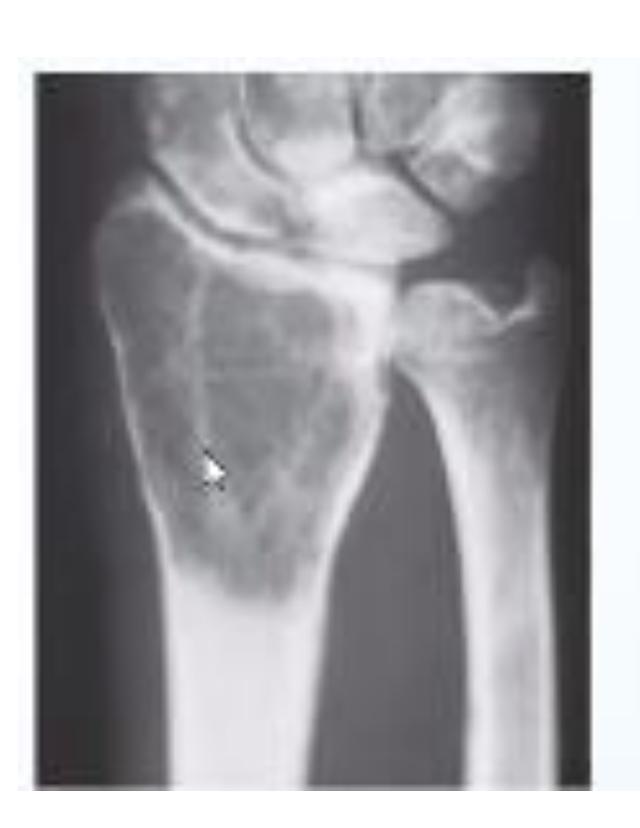

A teenager with acute onset of pain in the right hip during a run. He sustained the injury seen in the x-rays with a white arrow. This injury usually occurs due to a forceful eccentric contraction of which of the following muscles?

- C. Rectus femoris

- Sartorius

Pelvic Anatomy

Which of the following muscles is attached to the structure pointed by the arrow?

- C. Sartorius

Note: Arrow was pointing at ASIS (Anterior Superior Iliac Spine)